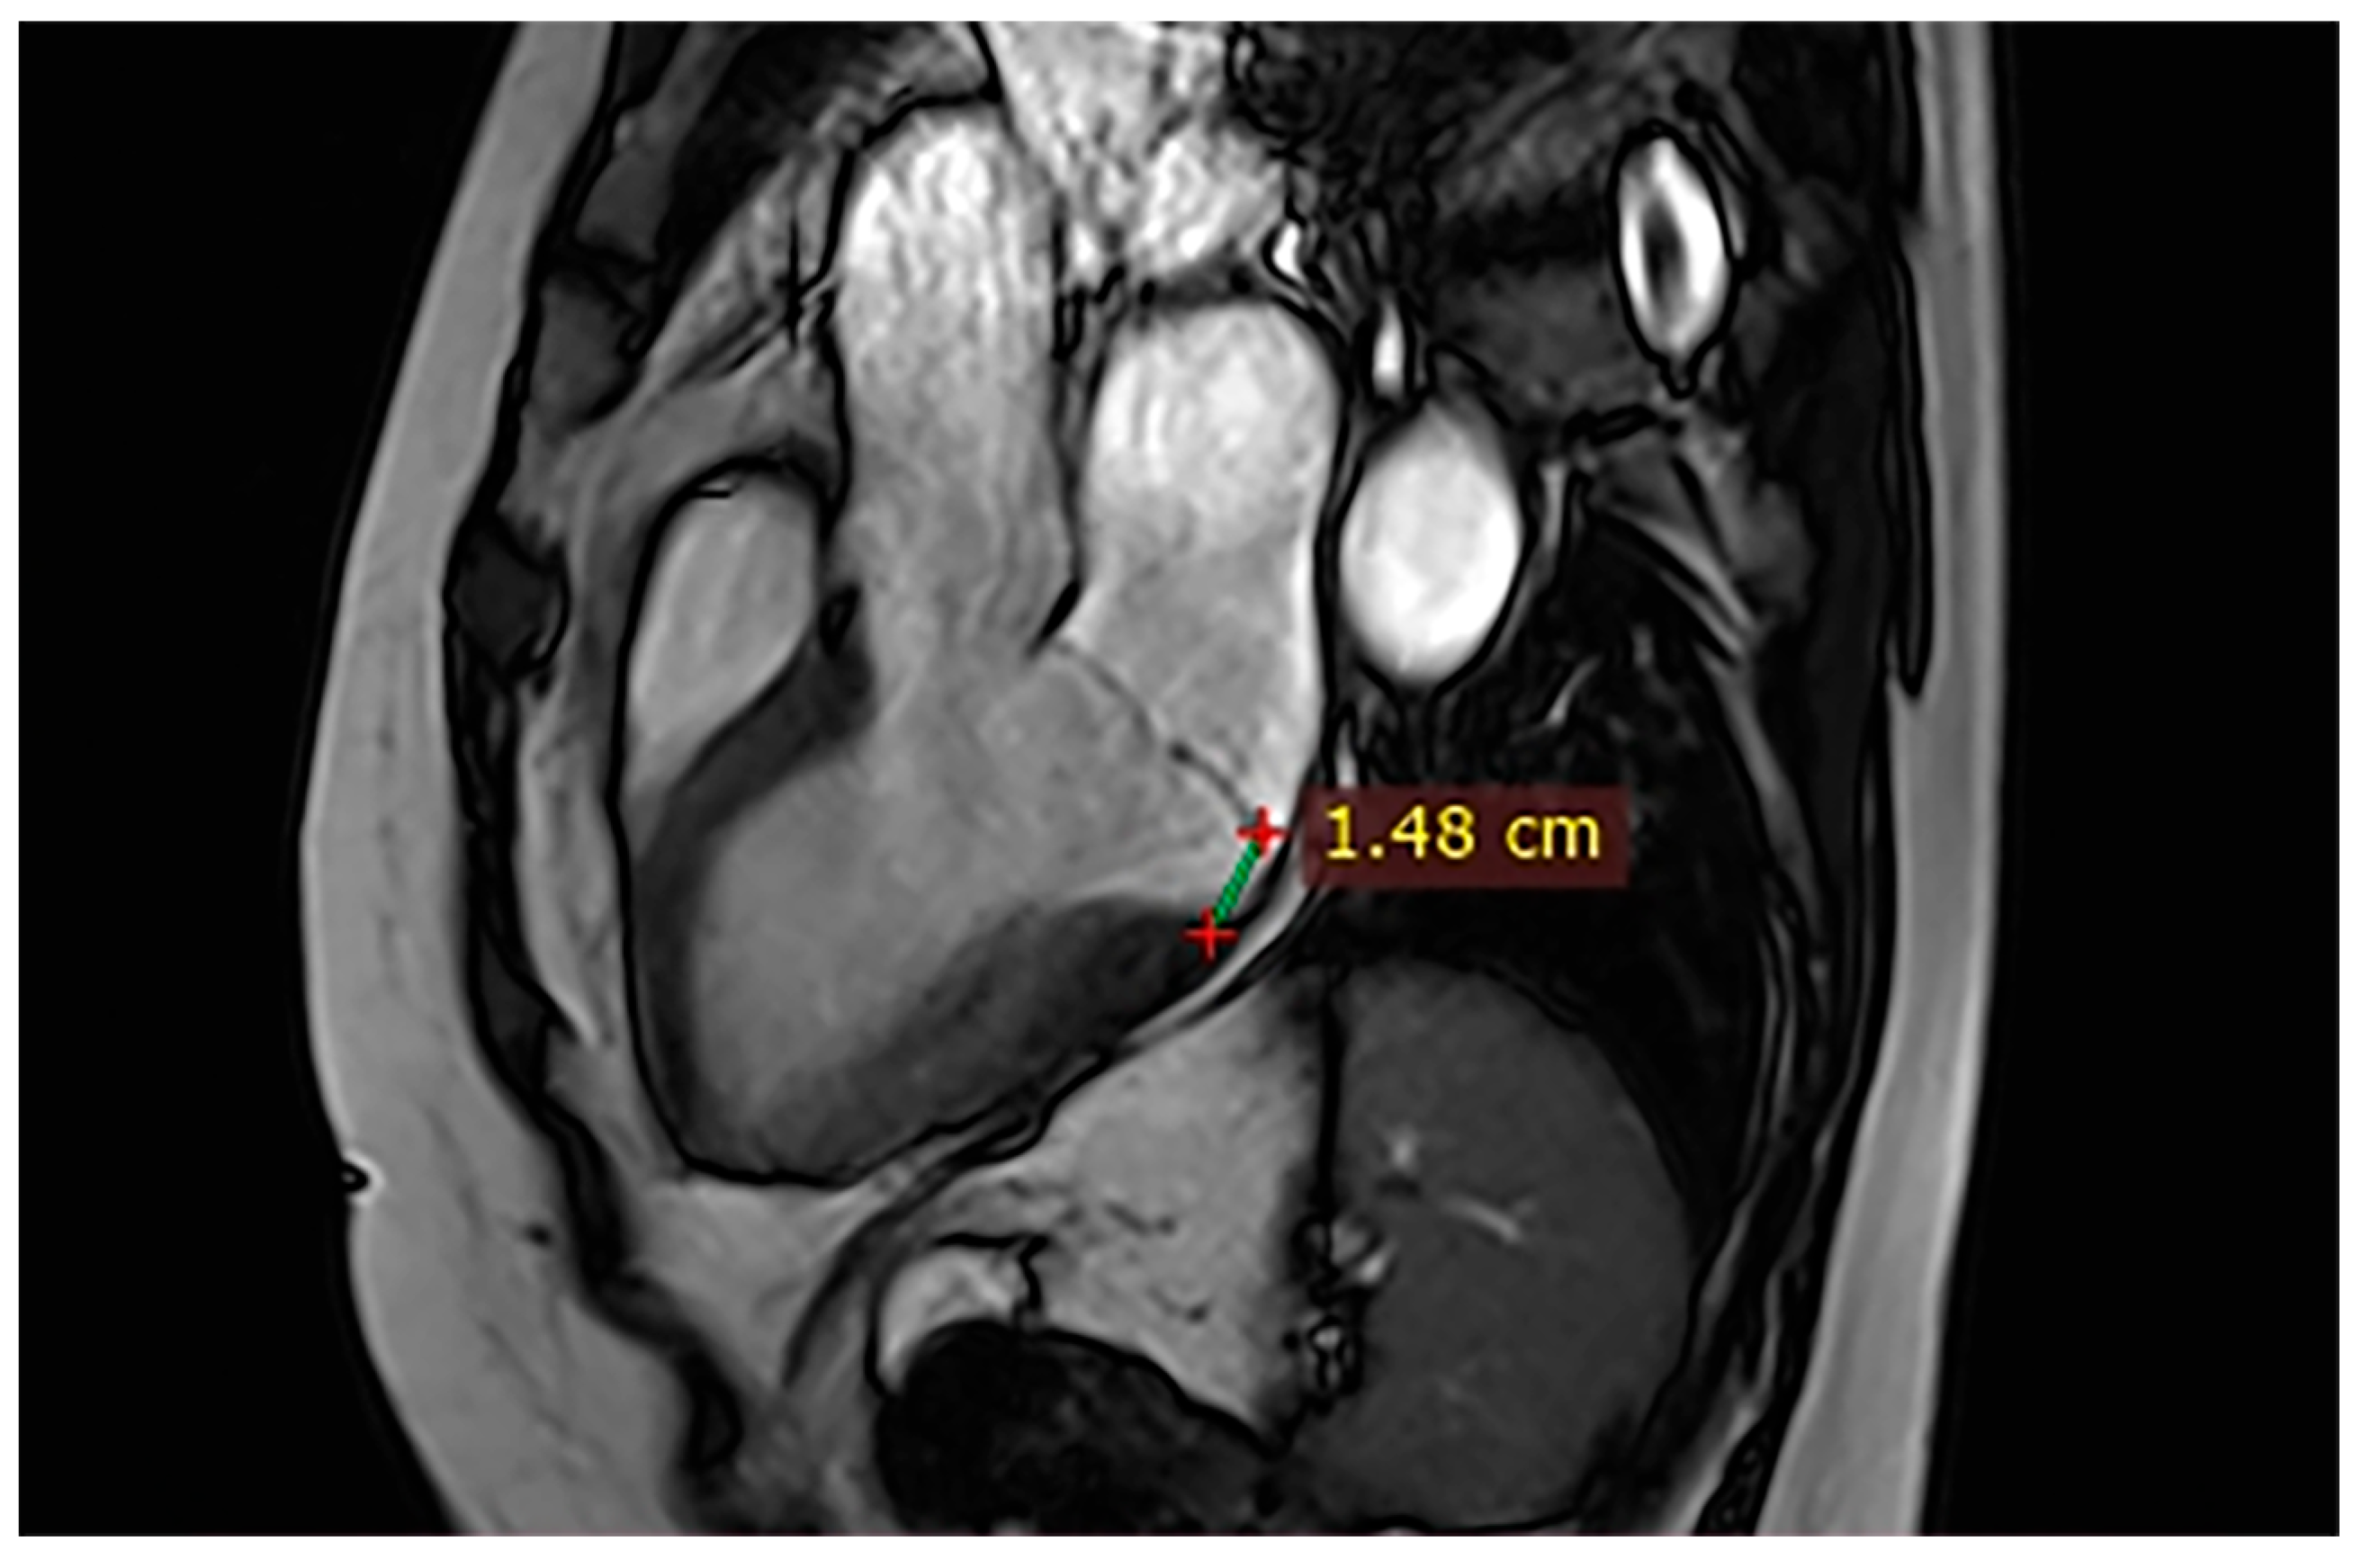

Case 2. A 52-year-old man with syncope and atypical chest pain had CMR showing mildly reduced LVEF (48%), a posterior MAD of 10 mm (Figure 3), and focal non-ischemic LGE in the basal lateral segments. Regular cardiology follow-up and Holter monitoring were recommended to assess arrhythmic burden.

Figure 3.

Cardiac magnetic resonance (CMR), three-chamber steady-state free precession (SSFP) cine. A 10 mm mitral annular disjunction (MAD) with associated mitral insufficiency is observed.